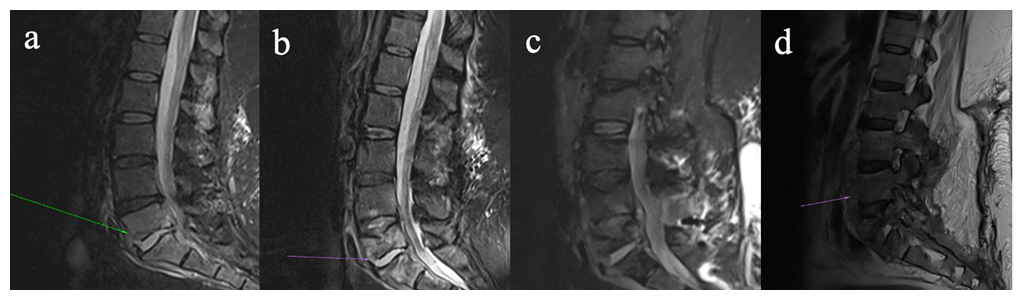

Figure 2Four-panel figure demonstrating progressive discitis/osteomyelitis involving the lower lumbar spine on magnetic resonance imaging (a–d). (a) Sagittal STIR images show discitis/osteomyelitis at L5/S1. (b) Sagittal STIR images now demonstrate progression of disease, with erosion of the L5 superior endplate, development of an anterior epidural collection, and associated ligamentum hypertrophy with resultant bunching of the distal cauda equina. (c) STIR image pre-instrumentation removal demonstrate a progressive discitis/osteomyelitis at L4/L5, with multiple enhancing collections within the anterior epidural space and posterior to the anterior longitudinal ligament. (d) Sagittal T2 images of the lumbar spine post-hardware removal demonstrate further destruction of the L5 vertebral body, with a persistent enhancing collection within the anterior epidural space, and a new collection along the anterior longitudinal ligament.

She re-presented 3 weeks later with pyrexia, drowsiness, and progressive lower back pain. A repeat MRI lumbar spine revealed L5/S1 osteomyelitis with bilateral multiloculated abscesses involving the iliopsoas muscles (Fig. 2a). Interventional radiology facilitated a biopsy of the L5/S1 disc space which identified M. abscessus complex. Peripheral blood cultures identified Mycobacteria species other than tuberculosis complex. Antimicrobial therapy (Fig. 1) was commenced with amikacin, linezolid, tigecycline, and meropenem, since imipenem and cefoxitin are not widely available in Ireland. Following multi-disciplinary discussion, surgical intervention was deferred as it was deemed high-risk given the absence of neurological symptoms. Based on drug susceptibility testing (DST) (Table 1), azithromycin and clofazimine were added to the regimen and linezolid was discontinued. Meropenem was stopped due to a suspected delayed hypersensitivity reaction. Following 3 weeks of antimicrobial treatment, repeat mycobacterial blood cultures were sterile.

Six weeks after starting antimicrobial treatment, she developed new loss of power in ankle dorsiflexion. A repeat MRI lumbar spine revealed an anterior epidural abscess at L4/L5, narrowing of the spinal canal, and bunching of the cauda equina (Fig. 2b). The acute cauda equina syndrome prompted emergent surgery for decompression and stabilization with pedicle screws and rods. Intra-operative tissue samples identified Mycobacteria species other than tuberculosis complex. Her dose of prednisolone was doubled to 30 mg prior to surgery as a stress dose which was tapered postoperatively. She completed induction antimicrobial regimen during her 4-month admission, and was discharged on azithromycin, clofazimine, and bedaquiline (Fig. 1).

At Infectious Diseases clinic follow-up, she endorsed worsening back pain and new skin lesions. A biopsy of the skin lesions showed acid-fast bacilli (AFB) on stains and isolated Mycobacterium abscessus complex (Table 1). Repeat MRI lumbar spine (Fig. 2c) displayed an increase in the paraspinal subcutaneous fluid collection (5.0×2.2×13 cm), but repeat mycobacterial blood cultures showed no growth. Amikacin and tigecycline were restarted, and the patient was transferred to the National Spinal Unit for surgical evaluation. Upon transfer, she underwent surgical debridement and washout with removal of spinal metalwork to achieve source control. Intra-operative samples showed AFB on smears, and M. abscessus complex was identified on culture (Table 1) and whole genome sequencing (WGS); however, subspeciation could not be performed.

Her postoperative course was complicated by severe pancreatitis, requiring admission to the intensive care unit (ICU), which led to the discontinuation of tigecycline and bedaquiline, tapering of prednisolone, and the addition of cefoxitin. Due to the limited antibiotic options for M. abscessus, the isolate was sent to a research laboratory in Cleveland Veteran's Affairs (VA) Medical Center, Ohio, United States of America, for β-lactam synergy DST. To decrease net immunosuppression, prednisolone was tapered to 10 mg d−1. Following discharge from ICU, she developed new skin nodules on her extremities, a biopsy of which showed necrotizing granulomatous inflammation; however, mycobacterial culture of the biopsy was negative and blood cultures were negative. Repeat imaging revealed multiple paraspinal collections concerning for abscess (Fig. 2d). No other sources of infection were identified throughout the hospitalization. Once imipenem was available, cefoxitin was switched to dual β-lactam (DBL) therapy with imipenem plus ceftaroline (Fig. 1).